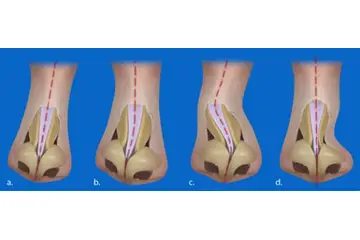

Kıkırdak Doku Çeşitleri Kıkırdak doku, bağ dokuları arasında yer alan, esnek ve dayanıklı bir yapıya sahip olan dokulardır. Farklı türleri ve işlevleri, vücudun çeşitli bölgelerinde önemli roller üstlenmektedir. Bu makalede, kıkırdak dokunun çeşitleri ve özellikleri detaylı bir şekilde ele alınacaktır. Kıkırdak Doku Türleri Kıkırdak doku üç ana türde sınıflandırılmaktadır: hyalin kıkırdak, elastik kıkırdak ve fibröz kıkırdak. Her bir tür, farklı yapısal özelliklere ve işlevsel amaçlara sahiptir.

Kıkırdak Dokunun Özellikleri Kıkırdak dokunun bazı ayırt edici özellikleri şunlardır:

Kıkırdak Doku ve Hastalıklar Kıkırdak dokunun sağlık durumu, birçok hastalığın gelişiminde önemli bir rol oynamaktadır. Osteoartrit gibi dejeneratif hastalıklar, kıkırdak dokusunun bozulmasıyla ilişkilidir. Ayrıca, kıkırdak dokunun yaralanmaları, spor yaralanmaları ve travmalar sonucunda meydana gelebilmektedir. Kıkırdak Doku Araştırmaları ve Gelecek Perspektifleri Günümüzde kıkırdak doku araştırmaları, doku mühendisliği ve yenileyici tıp alanında yoğunlaşmaktadır. Kıkırdak hasarını onarmak veya yeniden oluşturmak amacıyla hücresel tedavi yöntemleri ve biyomühendislik uygulamaları geliştirilmektedir. Bu alandaki ilerlemeler, kıkırdak ile ilgili hastalıkların tedavisinde önemli yenilikler getirebilir. Sonuç olarak, kıkırdak doku, vücutta önemli bir rol oynamakta olup, farklı türleriyle birlikte çeşitli işlevler üstlenmektedir. Bu yapıların sağlığı, genel sağlık durumu üzerinde önemli bir etkiye sahiptir ve araştırmalar bu alanda devam etmektedir. |